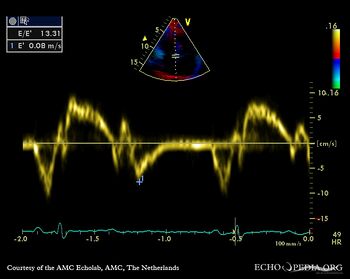

| TDI | |